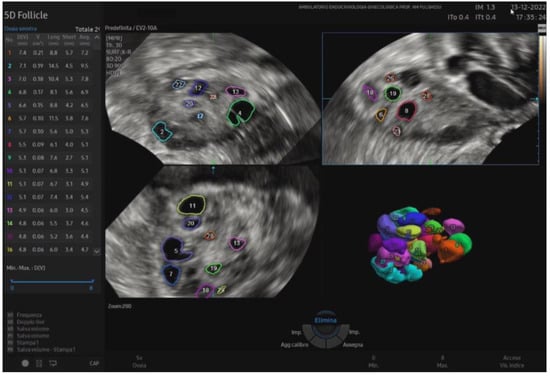

Recently, 3D ultrasound has gained increasing popularity in studying PCOS and reproductive medicine. It appears to provide a more reliable and objective assessment of ovarian volume and morphology, stromal area, follicle count, and overall blood flow than traditional 2D methods, as shown in Figure 2.

Figure 2.

A 3D study of the ovary: identification and measurements of the ovarian follicles to rapidly assess the size, follicular status, and spatial arrangement.

It offers a noninvasive, safe, and painless option for evaluating the internal genitalia in young women. Moreover, 3D ultrasounds can detect more follicles than 2D imaging, enhancing diagnostic accuracy [46,47]. In adolescents, where the diagnosis of PCOS remains uncertain after clinical and laboratory evaluation, magnetic resonance imaging (MRI) could be considered an alternative imaging modality. However, if 3D-TA approaches become widely available, with suitably high-resolution probes, 3D ultrasound may reduce the reliance on MRI in borderline cases [48]. Among the recently employed three-dimensional ultrasound techniques in evaluating the PCOM, inversion mode provides a highly effective way to highlight fluid-filled structures such as antral follicles. By virtually inverting the echogenic signals, the typically hypoechoic areas (e.g., follicular fluid) appear hyperechoic, allowing for easier follicle detection and quantification (Figure 3). This method can reduce the error in follicle counting, enhance the visualization of the follicular layout, and provide additional insights into the stromal–follicular relationship [49].

5.1. Advantages of 3D Software and Automated Follicle Measurement

The automatic measurement of follicular diameter using dedicated 3D software (HS40 s/w v.1.02) has multiple advantages over the traditional 2D technique. First, it shortens examination time since ultrasound data can be stored in toto and analyzed later. These data can be reconstructed in any plane, independent of the original scanning orientation, allowing for a more detailed and flexible evaluation. Furthermore, this innovative method reduces operator dependence in interpreting images, enhancing objectivity and minimizing interobserver variability [50]. A recent study in overweight PCOS patients supports this evidence. It showed that 2D TV-US underestimated ovarian volume and antral follicle count (AFC) compared to 3D TV-US and MRI [31]. Therefore, 3D ultrasound appears more accurate than 2D methods in specific populations, including overweight women, and may improve the diagnostic sensitivity for PCOS [51].